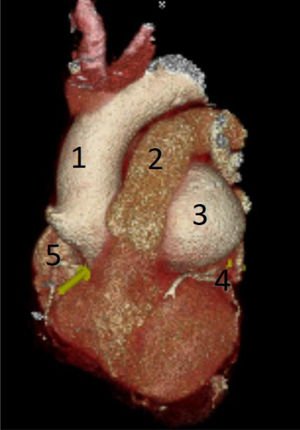

Realizamos una angiotomografía, la cual informó de un aneurisma de gran tamaño de seno de Valsalva izquierdo de 88,9 mm, que se encuentra por detrás del tronco de la arteria pulmonar y por delante de la aurícula izquierda. Se observa la coronaria izquierda saliendo en la porción distal del aneurisma. El cayado aórtico y la aorta descendente resultan con diámetros dentro de la normalidad (fig. 3).

Reconstrucción de tomografía donde se observa gran ASV izquierdo por detrás de la arteria pulmonar y por delante de la aurícula izquierda. 1) Aorta ascendente. 2) Tronco de arteria pulmonar. 3) ASV izquierdo. 4) Arteria coronaria izquierda. 5) Arteria coronaria derecha.

ASV: aneurisma de seno de Valsalva.